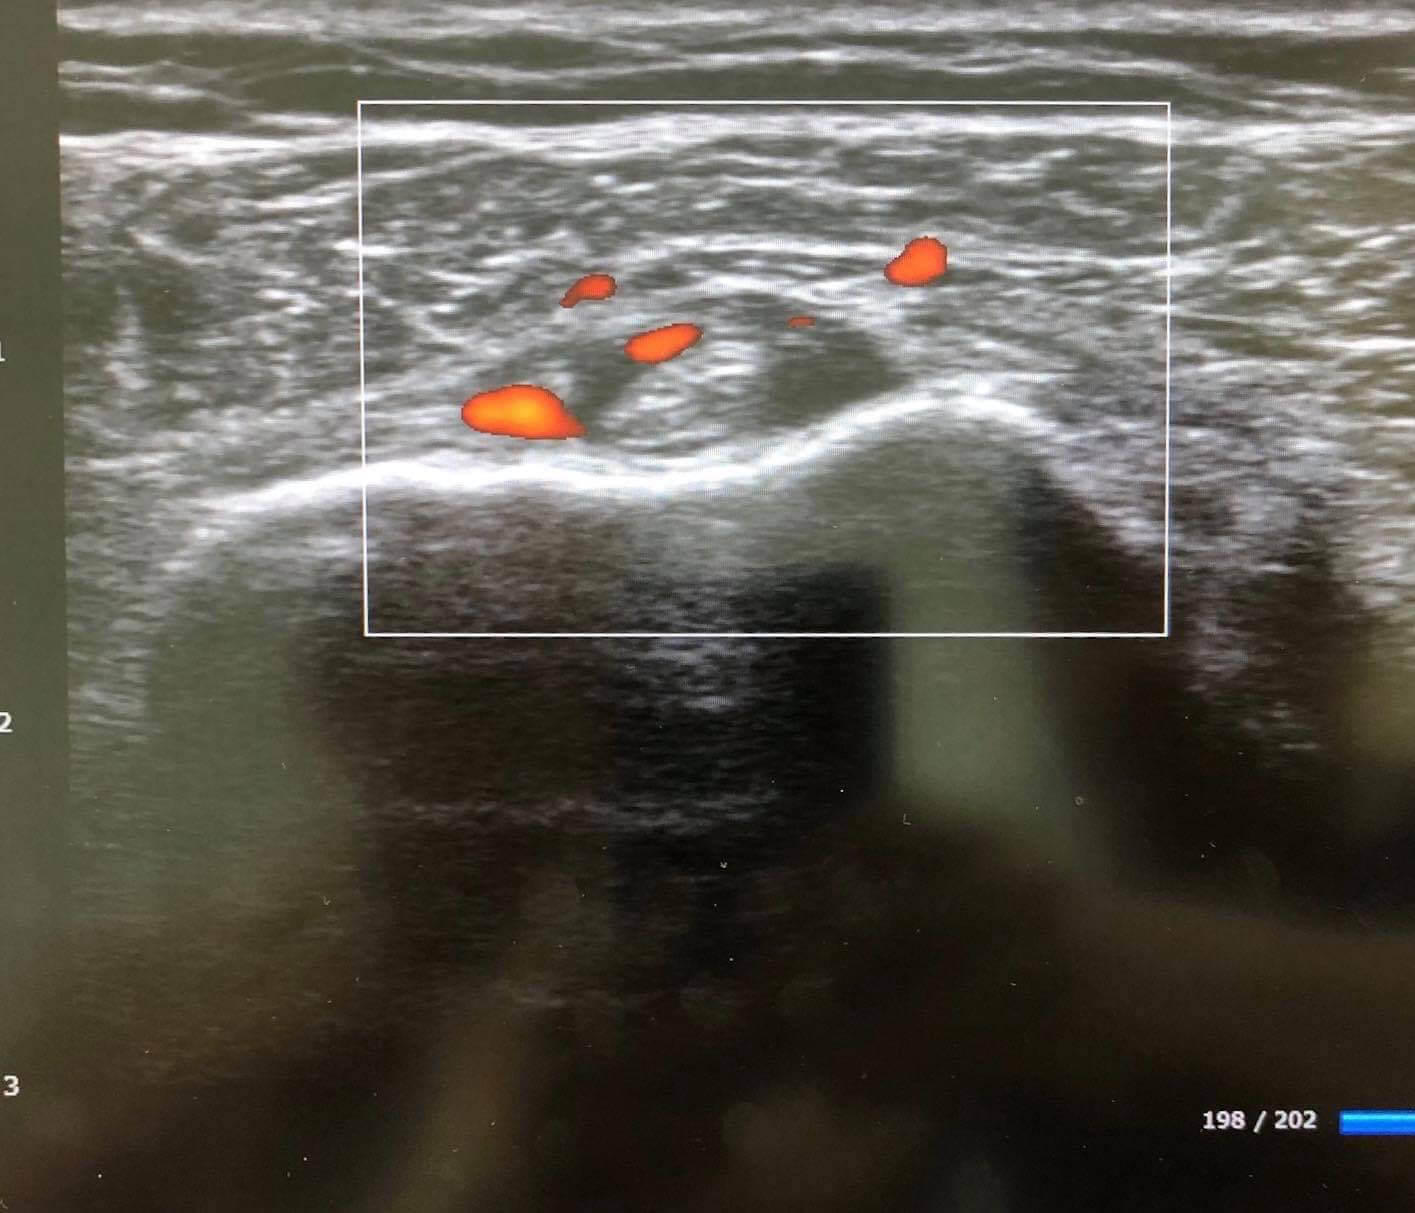

エコー検査とは、超音波を体内に当て、反射してくる音を受信して画像をつくり出す検査法である。そのなかのモードのひとつにドップラー法(Doppler method)がある。ドップラー法とは、近づいてくる音は高くなっていき、去っていく音は低くなっていくドップラー効果を応用して、炎症部位を同定するために用いられる検査である。この運動器エコーのドップラーモードを関節炎に応用した治療が、成果を上げているという。

「たとえば、40~50代に多い石灰沈着性腱板炎は、体内で自然にできる塩基性リン酸カルシウム(石灰)が肩関節の腱板に沈着することで起きますが、レントゲン撮影では石灰化していることはわかっても、肩の腱板のどこが炎症を起こしているかまではわかりません。しかし、エコーを併用すれば、モニターで炎症を起こしている部位を可視化できます」

運動器エコーによって炎症部を同定でき、そこへ直接、薬液を注入できるのがエコーの強みでもあると同時に、患者が自身の病態を理解しやすいという利点がある。

「患者さんにモニターを見せながら病状を説明できるのは大きなメリットです。漫然と痛み止めや注射を繰り返すことによるQOL(生活の質)の低下を防げます。注射の針もモニターで確認できるので、血管や神経を傷つけることもありません。レントゲンによる被曝の心配もないので、子供や妊婦にも安全に使用できます。運動器エコーは、検査だけではなく治療にも用いることができる画期的なツールなのです」